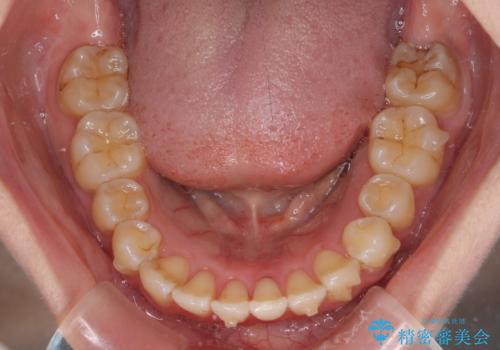

前歯のデコボコを解消 インビザラインによる矯正治療

- 上下前歯のデコボコと深い咬み合わせを気にして来院された患者様です。

インビザラインによる上下歯列の拡大と、IPR(歯と歯の間を削る)にるスペースの獲得により、前歯のデコボコを改善することとしました。

上の前歯をもう少し整えたかったのですが、患者様の治療を早く終了させたいという希望により、細かい叢生を残しての終了となりました。